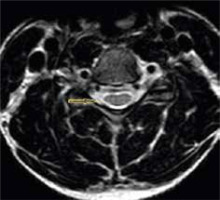

Figure 8

T2 axial section in a 22-year-old male with Hirayama disease in the neutral position showing loss of attachment of the posterior dura (arrow)

LOA of posterior dura with anterior displacement was seen in all the patients (100%) on flexion MRI (Figure 7). LOA involved the whole of the posterior dura (bilateral) in 13 patients (76.4%) and only one side in 4 patients (23.5%). Maximum LOA was seen at the C6 level in 10 patients (58.8%), followed by C5-6 intervertebral disc level in 5 patients (29.4%), and C5 and C6-7 level in one patient each (5.8%). This LOA of the posterior dura was seen in 11 patients (64.7%) on neutral position MRI, as well (Figures 8 and 9). On evaluating axial T2W and T2 FFE images for LOA of posterior dura, mutual consensus was reached by 2 radiologists that it was better visualised on T2 FFE images (Figure 9). The mean thickness of this LOA on flexion was 3.7 ± 0.66 mm (mean ± 2SD).

Asymmetrical lower cervical cord atrophy is the most important imaging feature on neutral MRI that can suggest the diagnosis of HD. LOA can also be seen on neutral MRI. On evaluating neutral T2W axial images in our study, LOA was seen to be present in 64.7% of the patients. As per Chen et al. [13], LOA was the most effective finding in the diagnosis of HD in neutral position MRI, with sensitivity and specificity greater than 93.5%; however, Lehman et al. reported lower sensitivity (70%) of this finding [18].